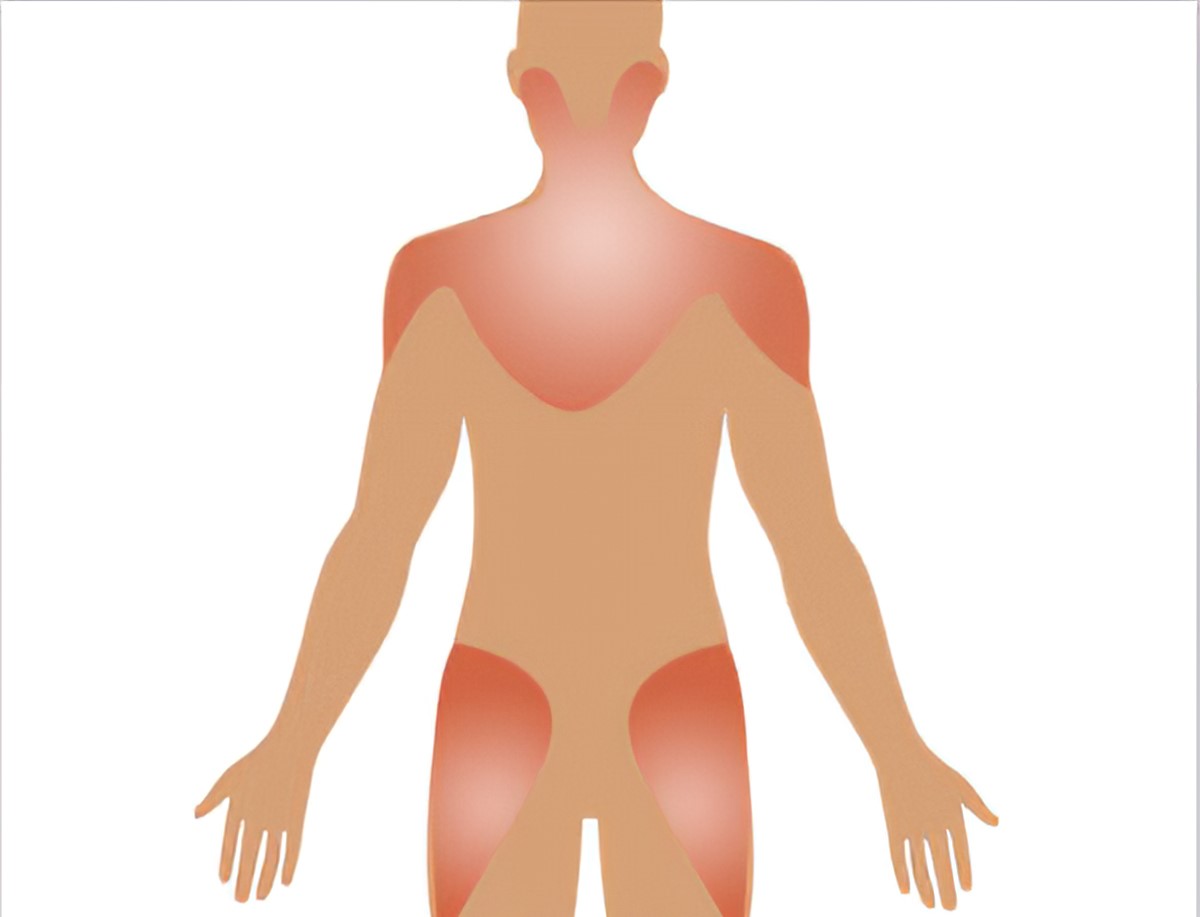

Soft tissue rheumatism:

Widespread pain

Fibromyalgia/ Fatigue

Shoulder pain/ Bursitis

Lateral hip pain/ Bursitis

Elbow pain/ Tennis elbow

Knee pain/ Knee bursitis

Back pain, neck pain

Myofascial pain syndrome

Foot pain/ Bursitis

Heel pain/ Plantar fasciitis